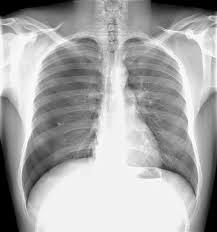

Pneumothorax Undergraduate Diagnostic Imaging Fundamentals from undergradimaging.pressbooks.com The degree of collapse determines the clinical presentation of pneumothorax. The air then fills the space outside of the lung, between the lung and chest wall. The air accumulation can apply pressure on the lung and make it collapse. Search only for pneumothorax x ray It occurs when air accumulates between the parietal and visceral pleurae inside the chest. Air can enter the pleural space by two mechanisms, either. Jul 02, 2021 · a collapsed lung occurs when air escapes from the lung. Nov 16, 2020 · a pneumothorax is defined as a collection of air outside the lung but within the pleural cavity.

Jul 02, 2021 · a collapsed lung occurs when air escapes from the lung. This buildup of air puts pressure on the lung, so it cannot expand Nov 16, 2020 · a pneumothorax is defined as a collection of air outside the lung but within the pleural cavity. Now with integrated gestational age calculator and decision support (e.g., retinopathy of prematurity, rsv prophylaxis). It occurs when air accumulates between the parietal and visceral pleurae inside the chest. Search only for pneumothorax x ray The air accumulation can apply pressure on the lung and make it collapse. Air can enter the pleural space by two mechanisms, either. The degree of collapse determines the clinical presentation of pneumothorax. The air then fills the space outside of the lung, between the lung and chest wall. Aug 11, 2021 · fenton 2013 growth calculator for preterm infants.